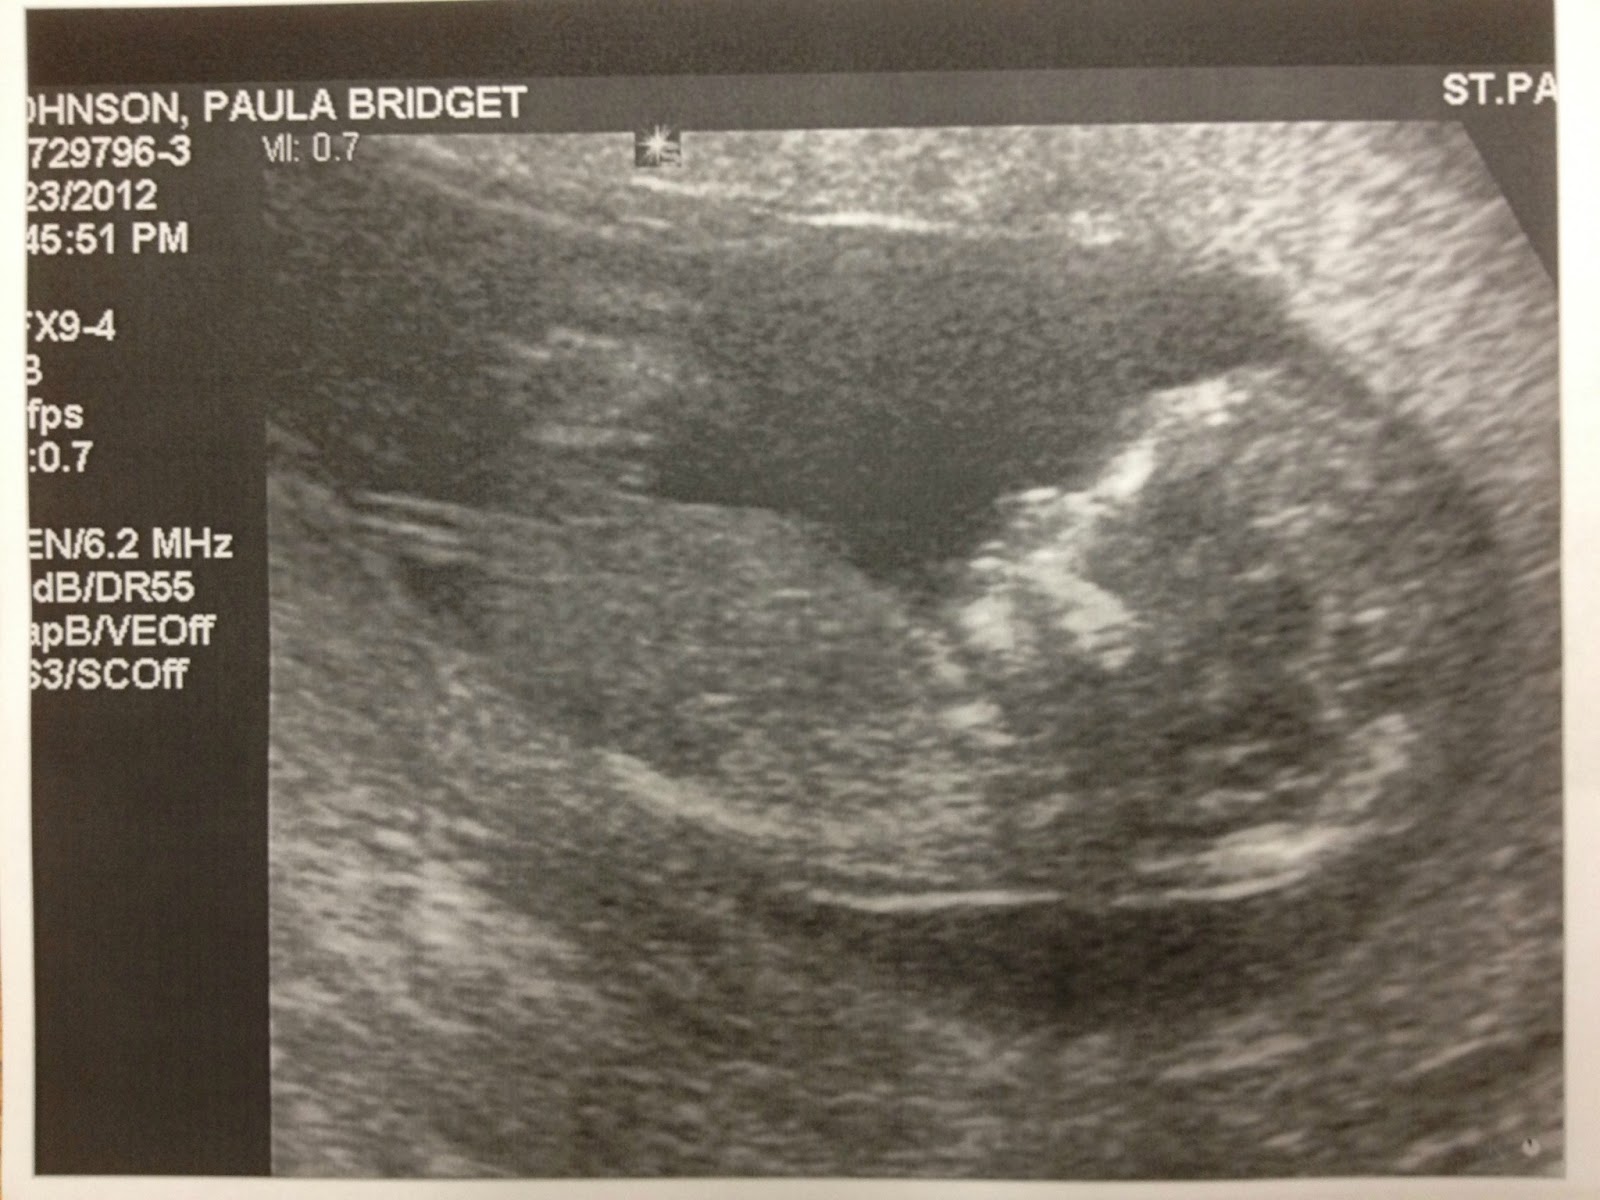

She changed my due date which was originally based on the first day of my last period from December 4th to November 27th which means I am week 14 now. That is good news for me! That means my morning sickness should be gone sooner. It supposedly ends week 14 and 15.

She took my blood pressure. I can't remember what it was but it was normal. Then I laid back and she took out a machine that amplified the heart beat of the baby. This is the first time we heard the heart beat. She said it was normal.